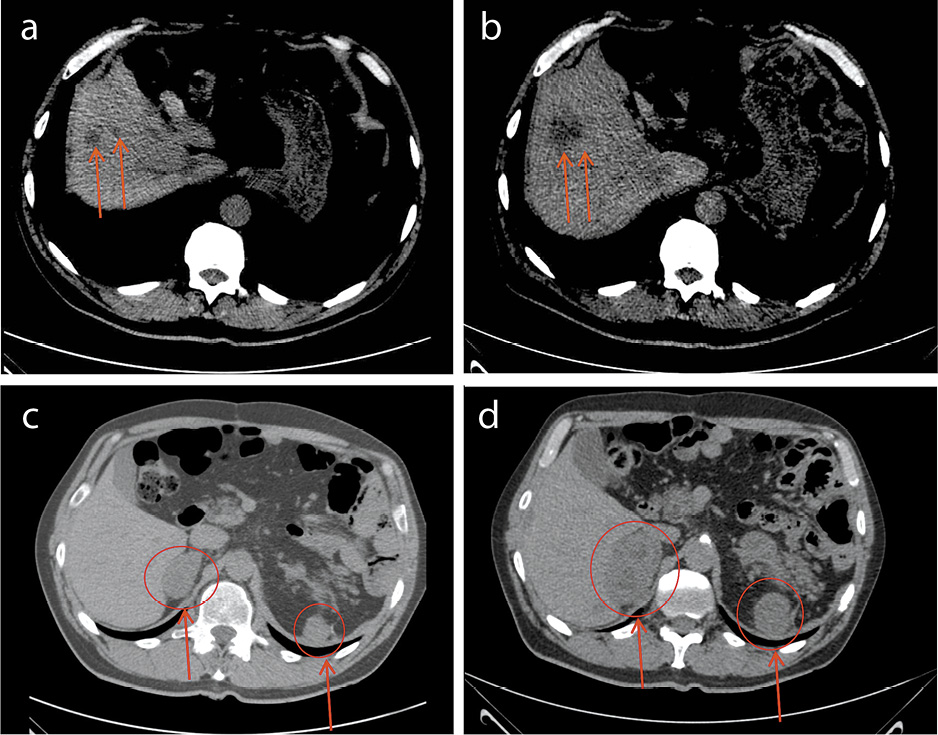

Пациент Б., 51 год. В 2006 г. диагностирована лимфома Ходжкина, нодулярный склероз I типа, IIВ стадия. В качестве терапии 1-й линии проведено 6 циклов по схеме ABVD и дистанционная лучевая терапия на область лимфоузлов средостения, шеи, подмышечных лимфоузлов справа. В 2012 г. – поздний рецидив заболевания. Проведена полихимиотерапия 2-й линии (схема IGEV) с последующей высокодозной химиотерапией и трансплантацией периферических стволовых кроветворных клеток (2013 г.). Второй рецидив – в 2016 г. Проводилась терапия бендамустином, схемами ChVPP (хлорамбуцил, винбластин, преднизолон, прокарбазин) и PEPC (прокарбазин, этопозид, преднизолон, циклофосфамид) без стойкого противоопухолевого эффекта. Ввиду прогрессирования заболевания в октябре 2018 г. начата иммунотерапия ниволумабом. После первого введения ниволумаба отмечено купирование В-симптомов. Самочувствие пациента оставалось стабильным на протяжении последующих 7 циклов иммунотерапии. После 8-го цикла у пациента появилась неврологическая симптоматика в виде слабости, уменьшения объема движений правой ноги, тяжести в правой половине живота, нарушения пассажа стула. По данным магнитно-резонансной томографии грудного отдела позвоночника в передней и паравертебральной области справа определяется массивный мягкотканый компонент протяженностью c ThIV до ThVI позвонков (6,5 cм), тотально заполняющий межпозвоночные отверстия справа, с компримированием дурального мешка на уровне ThIV–ThV–ThVI, спинной мозг неструктурен на уровне ТhV–ТhVI (рис. 4).

Рис. 4. Массивный мягкотканый компонент опухоли протяженностью c ThIV до ThVI позвонков: а – сагиттальная проекция; b – фронтальная проекция.

С учетом предшествующей положительной динамики после начала иммунотерапии (улучшение самочувствия, исчезновение В-симптомов) ситуация трактована как псевдопрогрессирование. Ухудшение после 8-го цикла ниволумаба объяснено сдавлением спинного мозга, увеличившимся на фоне псевдопрогрессирования мягкотканым компонентом. Гипотеза об имевшем месте псевдопрогрессировании оказалась верной. На фоне продолжения иммунотерапии пациент отметил регресс неврологической симптоматики, увеличение объема движений и силы правой ноги, восстановление пассажа стула. Феномен псевдопрогрессирования у пациента подтвердил и ретроспективный анализ исследований ПЭТ/КТ (рис. 5).